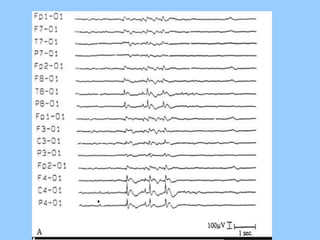

1. The document discusses EEG patterns and findings in various neurological conditions seen in children. It includes descriptions of normal EEG findings as well as abnormal patterns seen in conditions like absence seizures, West syndrome, benign childhood epilepsy with centrotemporal spikes, Lennox-Gastaut syndrome, non-convulsive status epilepticus, subacute sclerosing panencephalitis, and herpes encephalitis.

2. Case studies are presented with clinical histories and EEG findings to illustrate different pathologies. Treatment options are also mentioned for many of the conditions.